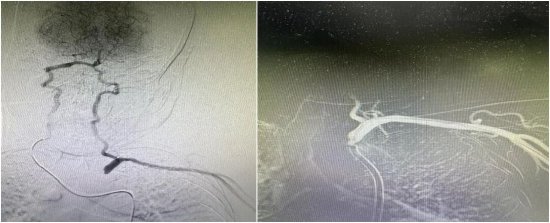

术后即刻造影显示:闭塞的血管重新开通,血流畅通无阻,左侧椎动脉恢复了正向供血。原本摸不到的左侧脉搏、乃至远侧桡动脉也恢复了有力跳动。

(支架顺利植入左锁骨下动脉开口处,造影提示左侧椎动脉正向血流恢复)